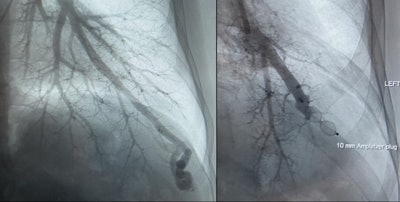

A particular interest of mine for over 20 years has been hereditary hemorrhagic telangiectasia (HHT), an inherited disease characterized by abnormal blood vessels in multiple body systems and organs. We run the national referral centre for HHT in Ireland in our hospital, and I've developed an expertise in management of pulmonary arteriovenous malformations (PAVMs) in these patients.

In this HHT patient treated at the Mercy University Hospital, a pulmonary AVM was diagnosed on angiography. Left image: before embolization procedure. Right image: after embolization.The techniques required to embolize PAVMs have particular nuances that make them fundamentally different from some other vascular malformations, and there are very specific considerations that must be borne in mind when screening HHT patients for PAVMs, and when treating and following them up. Being intimately involved in the care of this group of patients has been hugely rewarding and fulfilling.